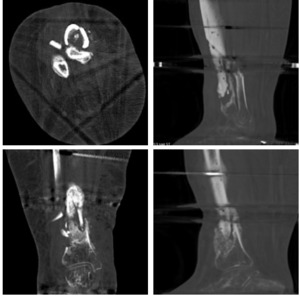

At thirty weeks, a CT scan demonstrated incomplete fracture healing with incomplete incorporation of the bone graft (Figure 5). The decision was made to maintain non-weightbearing and the skinny-wire frame to allow continued healing.

At thirty-three weeks, the patient presented to the emergency department with substantial right lower extremity pain and fevers. Subsequent radiographic imaging revealed he had broken one of the pins on his external fixator (figure 6). The external hardware was subsequently removed the next morning, giving the patient a hardware holiday while the definitive treatment was planned. MRI imaging revealed continued tibial nonunion and chronic osteomyelitis (Figure 7). Approximately one week later, the patient was taken for another I&D with excision of nonviable bone, placement of antibiotic coated tibial intramedullary nail, and placement of antibiotic cement spacer in the remaining tibial void measuring 7x3x3 cm (Figure 8). The patient was allowed partial weight bear postoperatively. Appropriate antibiotics were again determined from the intraoperative cultures by the infectious disease team, and at this time were positive for S. lugdenensis and S. agalactiae. He had made progress controlling his diabetes, as his most recent hemoglobin A1c was 4.5. Discussion with the patient was that this was a limb salvage procedure in an attempt to avoid amputation and that typically the cement spacer needs removal at a future date and replacement with bone graft.